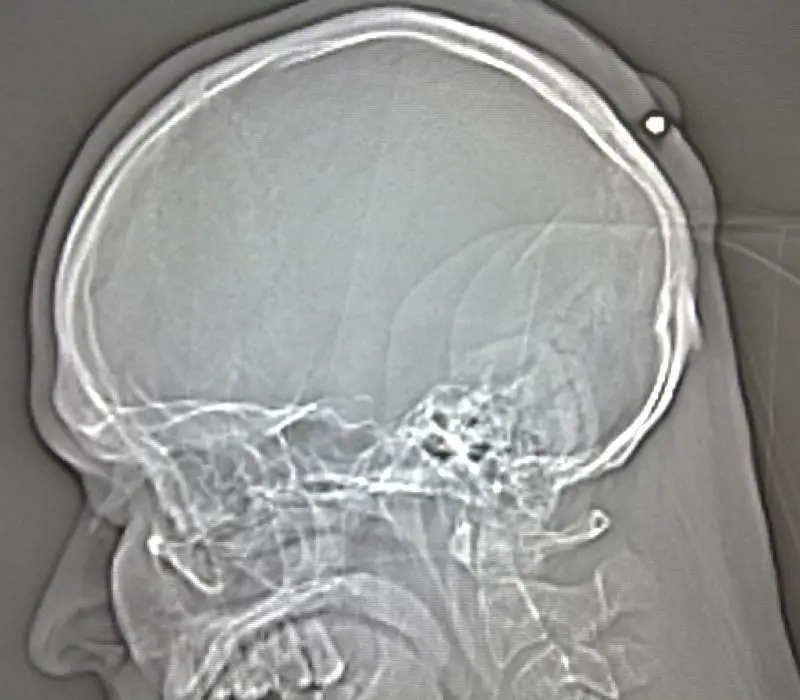

Berlino - Per oltre cinque anni ha vissuto con un proiettile conficcato nella nuca, ma non si è accorto di nulla fino a quando i medici a cui si è rivolto a causa di un forte mal di testa gli hanno trovato un proiettile calibro 22 intrappolato tra il cranio e la cute. La storia è quella di un polacco di 35 anni residente in Germania, che durante i festeggiamenti di capodanno di alcuni anni fa fu colpito da un proiettile vagante, senza rendersene conto perchè troppo ubriaco.

L'incredibile scoperta Alcuni giorni fa l’incredibile scoperta, effettuata dai medici della città tedesca di Bochum a cui l’uomo si era rivolto per farsi asportare quella che credeva fosse una cisti. Di fronte alle inequivocabili radiografie l’uomo si è ricordato di quando, durante una festa di capodanno in cui l’alcol scorreva a fiumi, avvertì un colpo dietro la testa. Un ricordo sbiadito tuttavia, tanto che l’uomo non ricorda neppure se si trattasse del capodanno del 2004 o di quello del 2005. "Ci ha detto di ricordare che avvertiva mal di testa, ma che non era nulla di così forte da richiedere l’intervento di un medico", ha raccontato uno dei medici citato dalla Bbc.

Secondo quanto dichiarato dagli esperti balistici della polizia il proiettile, rimosso dalla testa dell’uomo venerdì scorso, potrebbe essere stato sparato in aria conficcandosi poi nella testa durante la discesa. L’uomo, residente in Germania da diversi anni, resterà in ospedale ancora per alcuni giorni.